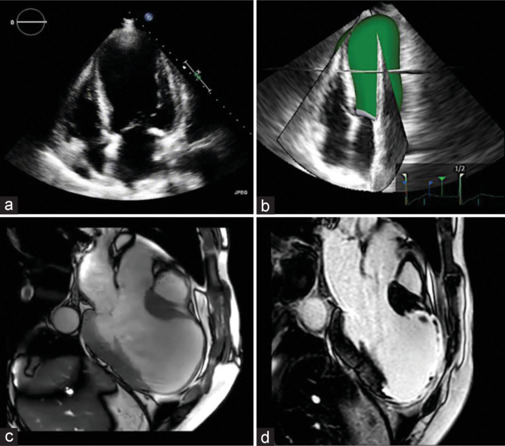

心源性猝死(SCD)的风险分层是一个多参数的过程,它整合了来自家族史、临床评估、心电图结果、心律失常负担和心血管成像的数据。超声心动图是SCD相关心血管疾病诊断和危险分层的一线成像方式。超声心动图和多模态成像技术的进步已经确定了一些参数,这些参数在SCD风险分层中具有可靠的预后价值。CMR =心脏磁共振,CT =计算机断层扫描,ECG =心电图,ECHO =超声心动图。

Risk stratification for sudden cardiac death (SCD) is a multiparametric process that integrates the data from family history, clinical evaluation, electrocardiographic findings, arrhythmic burden, and cardiovascular imaging. Echocardiography is the first-line imaging modality for both diagnosis and risk stratification of cardiovascular diseases associated with SCD. Advances in echocardiography and multimodality imaging have identified a number of parameters with proven prognostic value in SCD risk stratification. CMR = Cardiac magnetic resonance, CT = Computed tomography, ECG = Electrocardiogram, ECHO = Echocardiography.